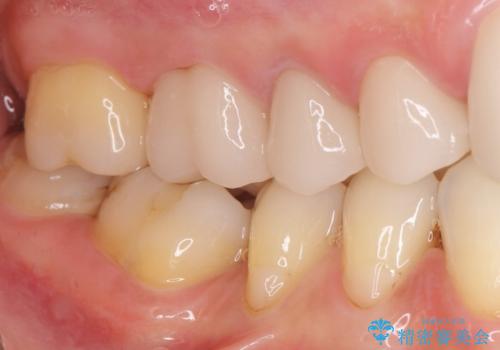

丁寧にう蝕除去と再根管治療を行い症状の改善を確認したのち、セラミッククラウン及びセラミックインレーによる補綴を行いました。

まるで天然歯のような自然な見た目と咬み心地にご満足頂けました。

気にされていた違和感もなくなり、喜んで下さいました。

クラウンの種類:オールセラミッククラウン スタンダード